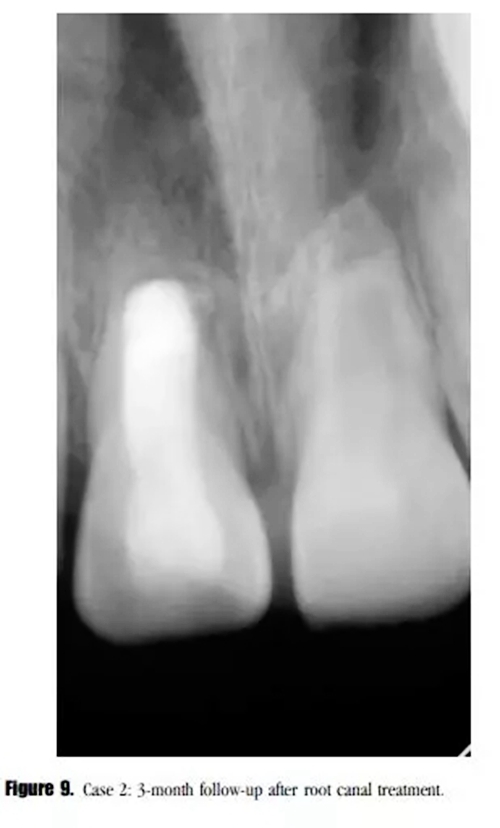

在3個(gè)月的隨訪中,患者癥狀消失,X線顯示透射區(qū)愈合(圖9)